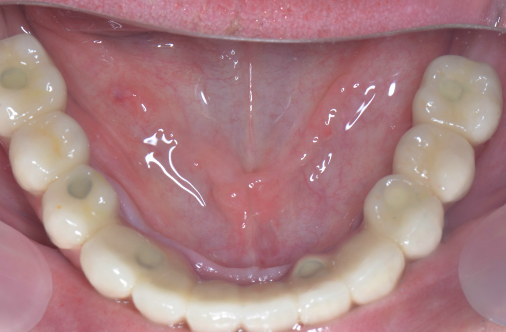

Lucrarea finală se va înșuruba pe componentele protetice ale implanturilor (Fig. 3.6.10 și 3.6.11), iar perforațiile de acces pentru șuruburi (Fig. 3.6.12) vor fi acoperite cu material compozit (Fig. 3.6.13). După fixarea definitivă (Fig. 3.6.14) puntea poate fi oricând detașată de către medicul dentist la nevoie, prin simpla îndepărtare a materialului compozit și desfiletarea șuruburilor de fixare.